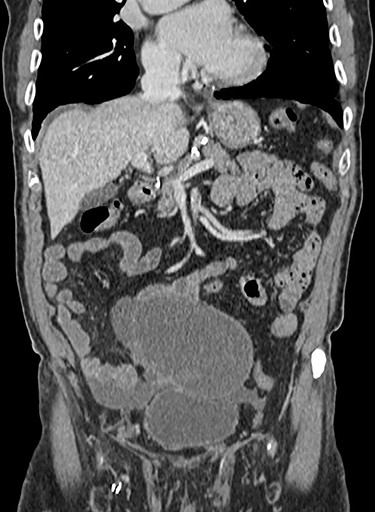

Following discussion with the patient and his relatives and obtaining informed consent, we proceeded with an elective diagnostic laparoscopy. At laparoscopy a large ruptured cyst possibly arising from the appendix was seen as shown in Fig. 2. There was free mucin in the right paracolic gutter and pelvis. Intraoperatively, the decision was made to proceed to a midline laparotomy for debulking and washout. The cystic mass, appendix and lateral peritoneum were excised and washout cleared all visible mucin deposits.

Resected mucinous appendiceal adenocarcinoma with areas of LAMN and HAMN.

Post-operatively the patient was discharged on day 6 and had an uncomplicated recovery. Post-operative pathology examination revealed a foci of appendiceal rupture and confirmed the suspected mesenteric cyst was in fact a moderately differentiated mucinous appendiceal adenocarcinoma arising on a background of LAMN and areas of HAMN. Staging was determined as pT4a NX xM1c R1 following intraoperative findings, imaging and pathology reports.